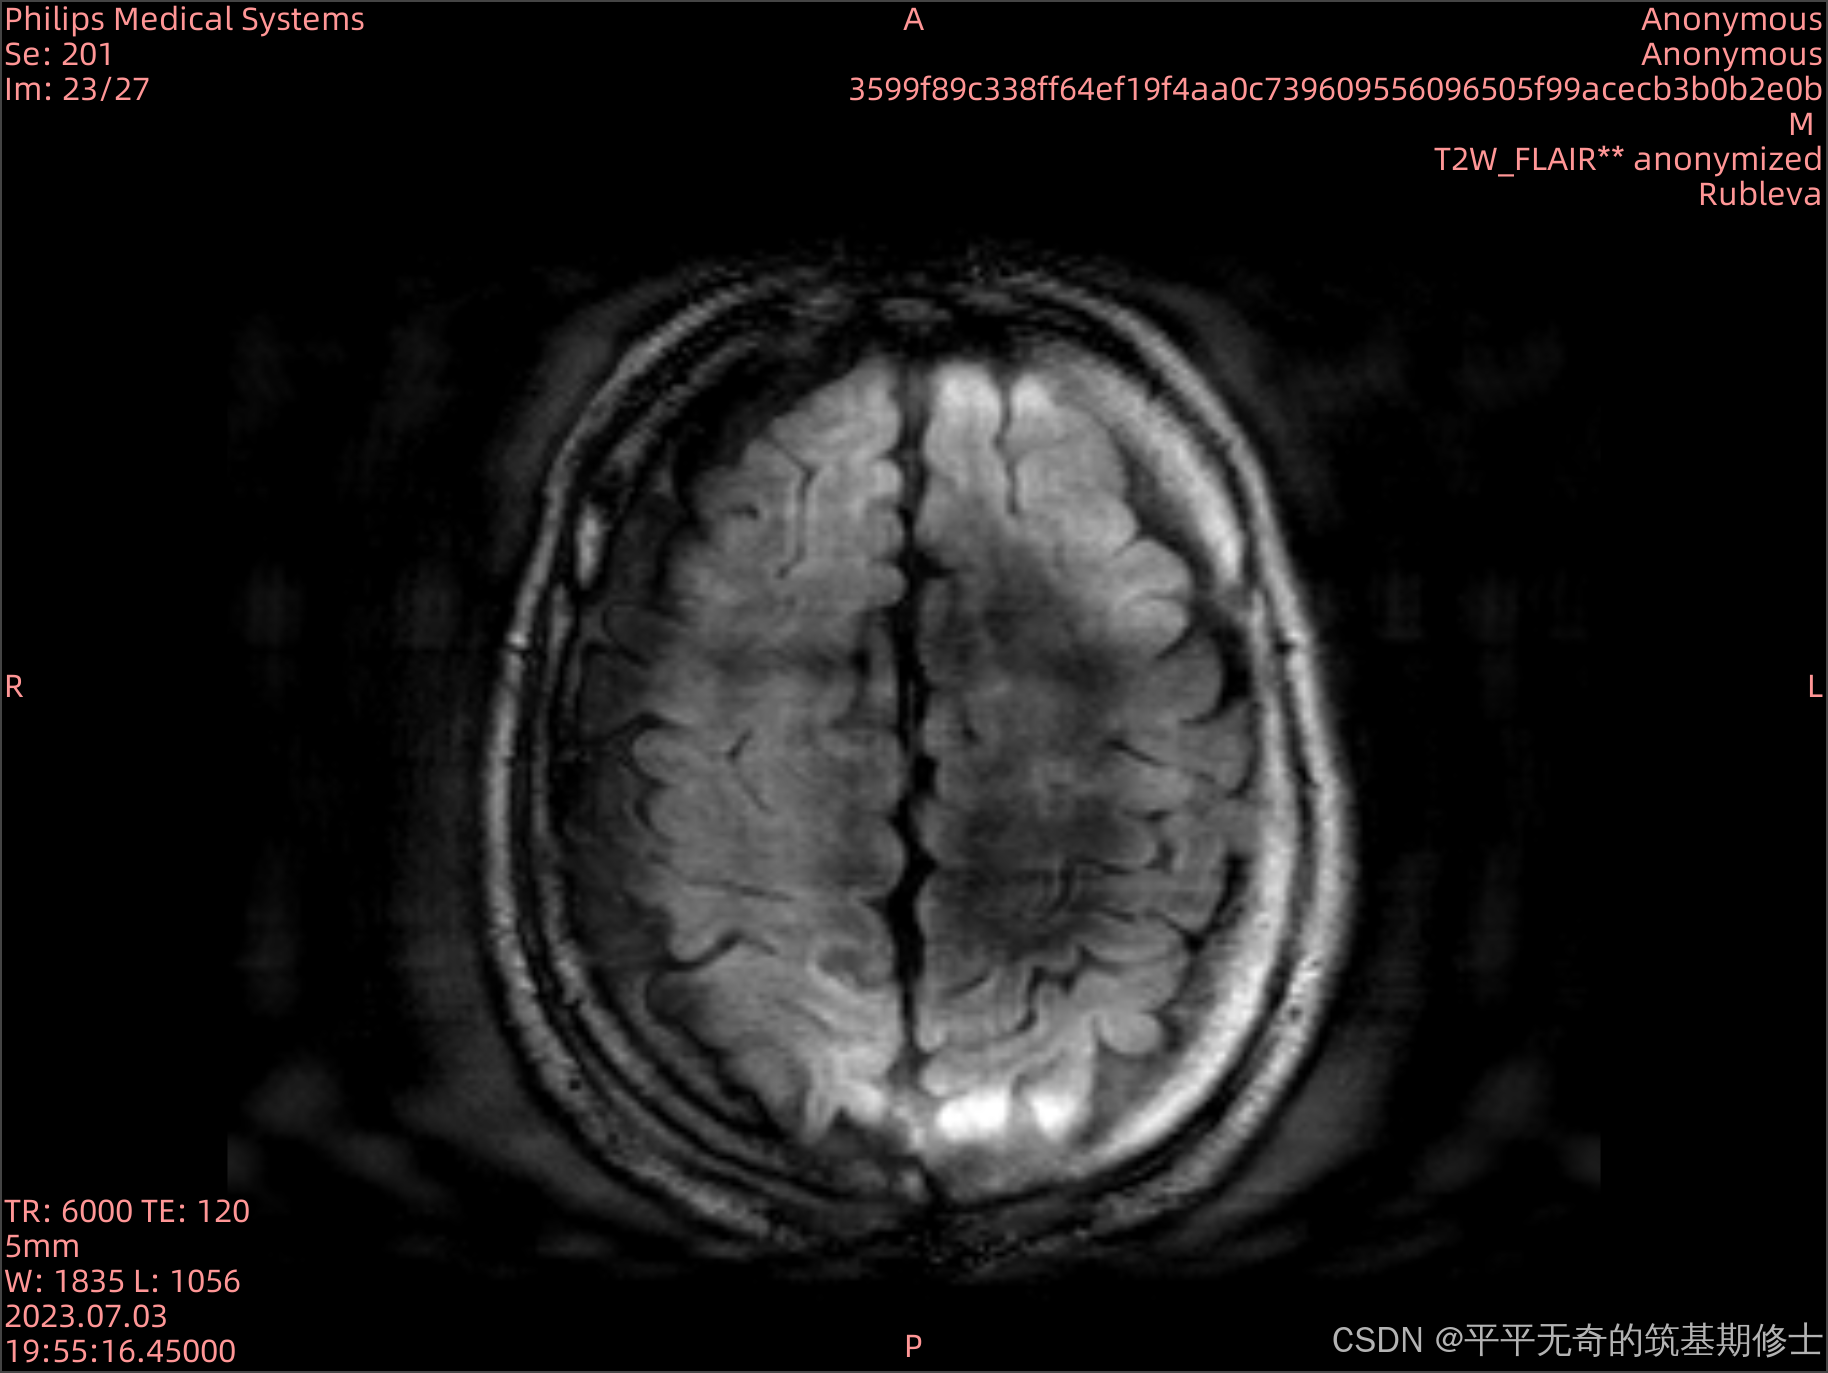

在医学影像中,运动伪影是一种常见的问题,特别是在MRI图像中。这种伪影会影响医生的诊断准确性。为了解决这一挑战,我们开发了一个伪影模拟工具,帮助研究人员分析和减轻伪影的影响。

代码实现了3D MRI图像伪影的模拟,涉及图像频域变换、随机运动轨迹的模拟以及伪影生成的逻辑。是一个医学成像中的运动伪影生成项目。核心功能集中在利用FFT、随机运动模拟和空间变换算法实现图像的随机扰动。

本项目的主要应用领域是医学影像模拟,特别是MRI图像中的运动伪影研究。它适用于:

- 图像分析:研究运动伪影对图像质量和诊断准确性的影响。

- 教育与培训:为医学影像学的教育与研究提供真实的运动伪影数据。

通过load_dicom_as_3d函数,将DICOM格式的切片加载并堆叠为三维数组。此步骤对切片进行排序并提取像素间距信息,确保影像的空间一致性。

- 通过FFT和随机运动轨迹生成伪影,模拟出更接近真实场景的三维MRI影像。